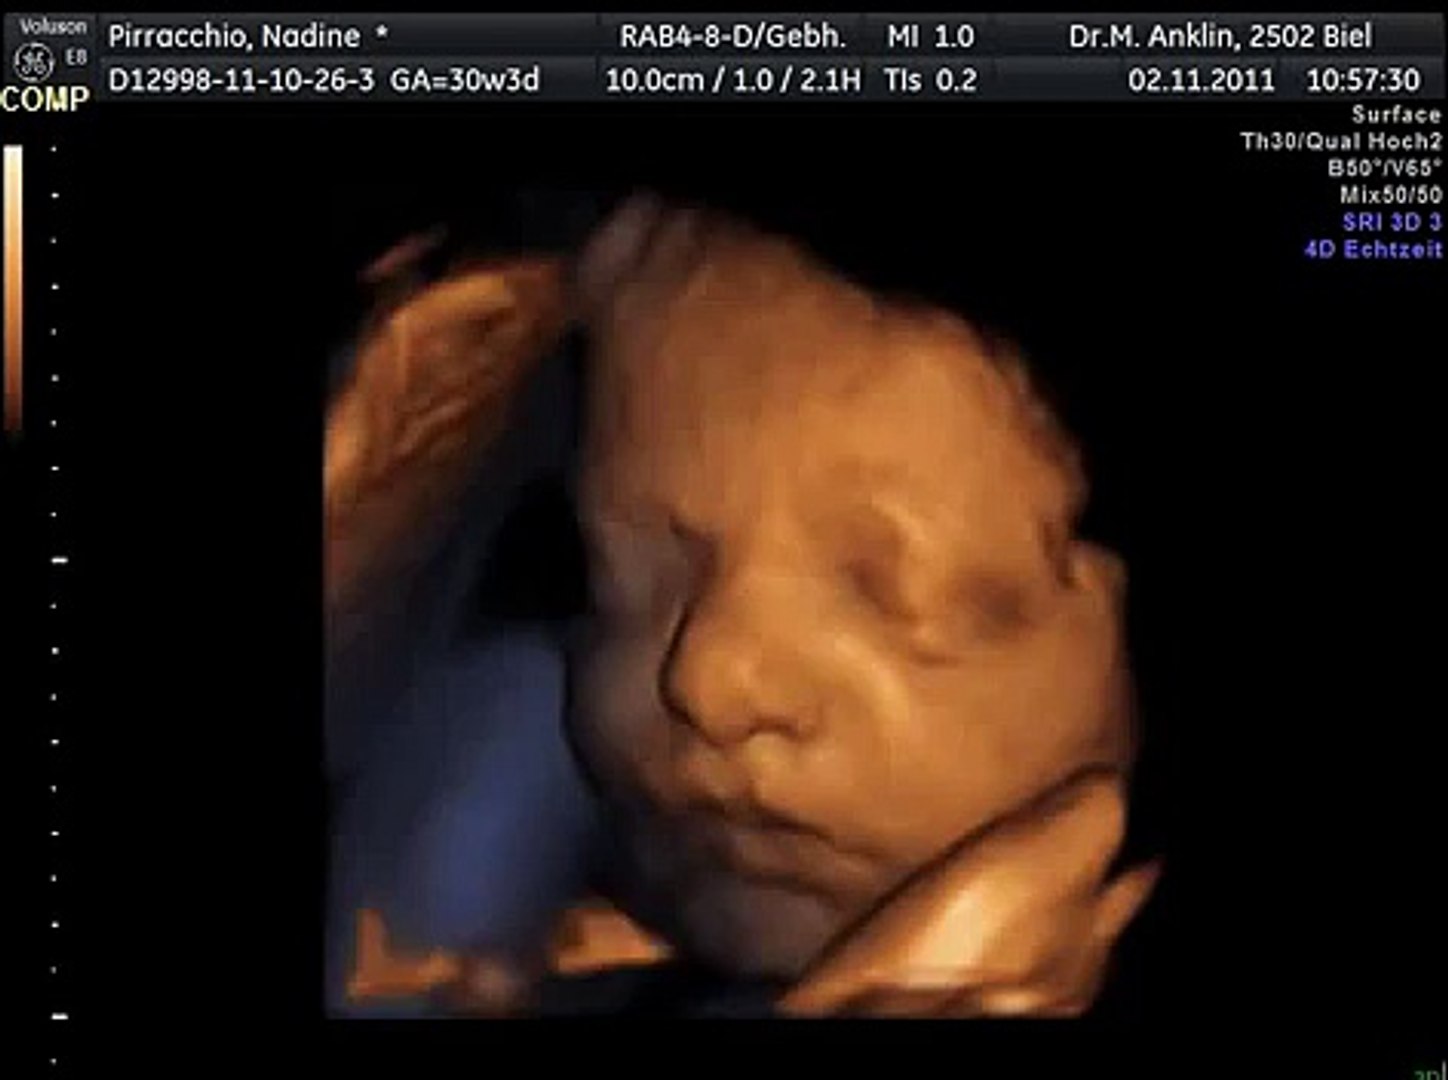

3d 4d Ultraschall Unser Sohn 28 Woche Ssw 27 6 5 By Puepper